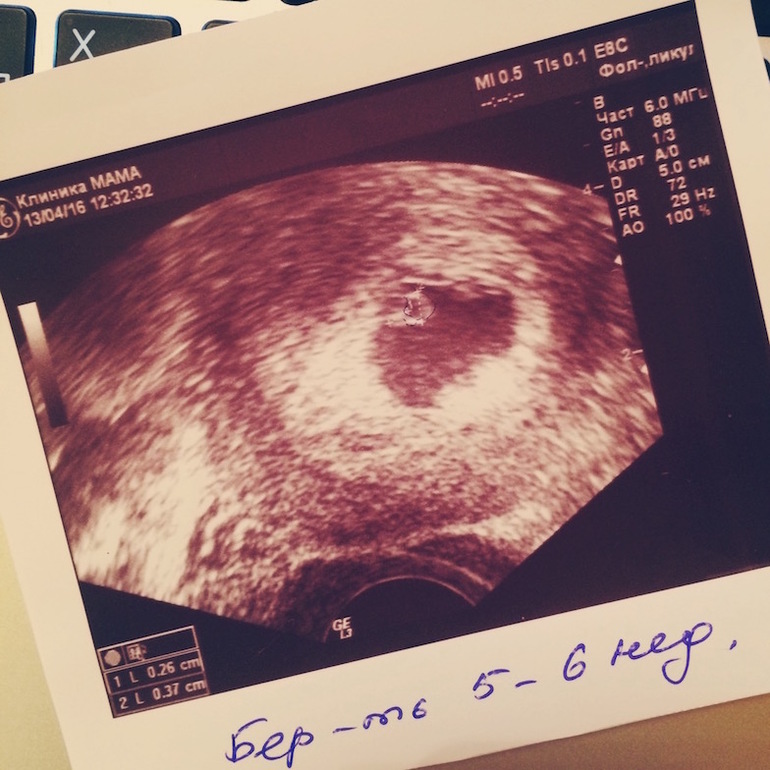

Наше первое УЗИ (23 дпп)

Ну вот я и посмотрела на сердечко моей маски - одна, правда, второй не видать. Махонькая совсем - 2,6 мм, но сердечко стучит! Девочки, это прекрасно! И еще у нас гематома какая-то - на сохранение сказали положат. 5-6 недель и уже на сохранение. Расстроилась. Вот такой у нас старт.

Фото маськи: